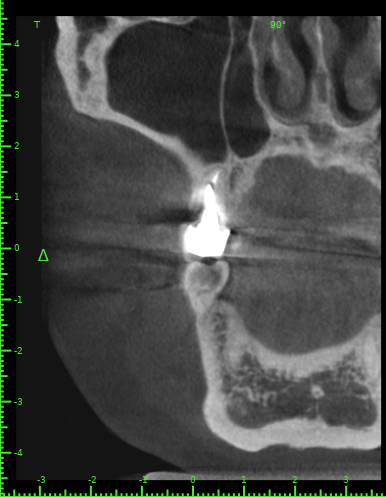

Katya88 Опубликовано 28 июля, 2021 Поделиться Опубликовано 28 июля, 2021 Мой стоматолог терапевт советует удалить, так как там кисты, а ортопед советует найти того, кто займется лечением. КТ прилагаю https://drive.google.com/file/d/1Z-neEH63BszTXxa8bAOG1tgsrIrsqrVK/view?usp=drive_web Ссылка на комментарий

Женька Опубликовано 28 июля, 2021 Поделиться Опубликовано 28 июля, 2021 2.6 2.7 3.7 На 3.5 и 1.5 стоит обратить внимание 1.5 1 Ссылка на комментарий

Женька Опубликовано 28 июля, 2021 Поделиться Опубликовано 28 июля, 2021 54 минуты назад, Katya88 сказал: 1.5 менять коронку как минимум снять существующую конструкцию и посмотреть клинически на зуб(ы). 1.5 на КТ выглядит удручающе. По остальным, я бы поддержал ортопеда и попытался зубы сохранить. Пусть коллеги меня поправят. 1 1 Ссылка на комментарий